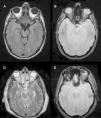

ResultadosEn las secuencias T2, FLAIR y EGRT2* se visualizan las LAD de manera adecuada en más del 80% de los casos. En FLAIR se visualizan mejor las LAD hemisféricas a nivel subcortical y el EGRT2* resalta las LAD hemorrágicas. En nuestra serie hemos visto que el grado de concordancia para diagnosticar LAD entre las secuencias T2, FLAIR y EGRT2* es alto (0,8). La secuencia T2 es la que tuvo un valor más alto en las curvas ROC tanto en la clasificación de Gentry (0,68; IC 95%: 0,61-0,76; p<0,001, Nagerlkerke-R2 0,26) como en la de Firsching (0,64; IC 95%: 0,57-0,72; p<0,001, Nagerlkerke-R2 0,19), seguida de la secuencia FLAIR y de la EGRT2*. Se observó, tras realizar un análisis multivariable, que las clasificaciones de Gentry y Firsching determinadas de forma independiente en cada secuencia se relacionaban con el pronóstico final de los enfermos al año del traumatismo (p<0,02).

ResultsTAI lesions were adequately visualized on T2, FLAIR and GRET2* sequences in more than 80% of the studies. Subcortical TAI lesions were well on FLAIR and GRET2* sequences visualized hemorrhagic TAI lesions. We saw that these MR sequences had a high inter-rater agreement for TAI diagnosis (0.8). T2 sequence presented the highest value on ROC curve in Gentry (0.68, 95%CI: 0.61-0.76, p<0.001, Nagerlkerke-R2 0.26) and Firsching classifications (0.64, 95%CI 0.57-0.72, p<0.001, Nagerlkerke-R2 0.19), followed by FLAIR and GRET2* sequences. Both classifications determined by each of these sequences were associated with poor outcome after performing a multivariable analyses adjusted for prognostic factors (p<0.02).